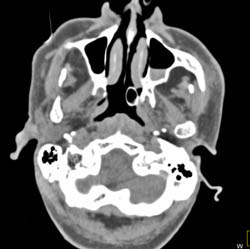

Sinusitis